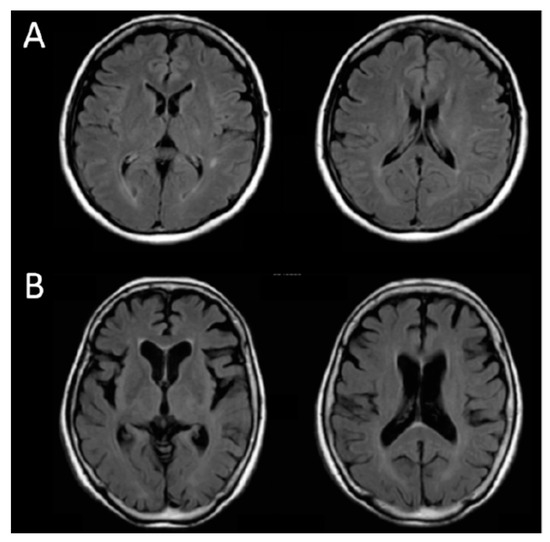

The degree of brain atrophy affected the OPLs. Figure 1 compares MRI images (fluid attenuated IR) of subjects with no brain atrophy (A) and severe brain atrophy (B). Table 5A compares the MMSE scores and VRSAD scores between no brain atrophy (Case A) and severe brain atrophy (Case B). The subarachnoid space in case B is larger than that in case A due to brain atrophy. Interestingly, the OPLs in case B were shorter than those in case A (Table 5B).

Figure 1. MRI images (fluid attenuated IR) of subjects with (A) no brain atrophy and (B) severe brain atrophy.